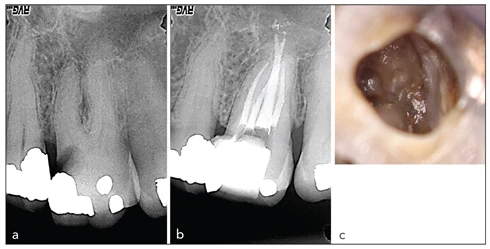

Hình 21-5: Răng cối lớn thứ nhất hàm trên với bốn ống tủy chính và một ống tủy hàm ếch bị chia đôi. Phim X-quang chẩn đoán (a) và sau điều trị (b). (c) Hình ảnh lâm sàng cho thấy hai lỗ ống tủy gần ngoài.

Hình 21-6: Răng cối lớn hàm dưới với bốn ống tủy, trong đó ống tủy xa thứ hai không phát hiện được ở lần đánh giá ban đầu. Phim chẩn đoán (a) và sau điều trị (b). Hình ảnh lâm sàng cho phép khẳng định sự hiện diện của ống tủy xa thứ hai (c).